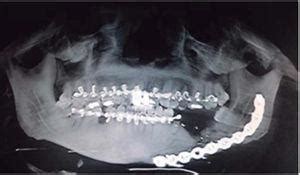

Respetando los pasos de protocolo quirúrgico sin colgajo, valiéndonos de bisturís circulares de diámetros similares al del implante a insertar en cada sitio, se colocan los implantes con la ayuda de una llave dinamométrica graduada en 40 Nw, para asegurar una fijación primaria, y se realiza una radiografía panorámica de control. Previamente se habían elegido los aditamentos protésicos que se atornillarían sobre los mismos. Luego de colocados en boca, se realizan las correcciones necesarias para mejorar el paralelismo de los muñones entre sí y para favorecer el ajuste pasivo de la prótesis a colocar sobre ellos.

Radiografía panorámica postquirúrgica

Aditamentos protésicos atornillados a 35 Nw sobre los implantes

La prótesis provisional confeccionada previamente, en el laboratorio dental en base a nuestro encerado diagnóstico, elaborada en resina acetálica radioopaca y rebasada con resina fotopolimerizable para poder lograr un ajuste sin tensiones, se presenta en boca para realizar los ajustes oclusales necesarios, tanto en céntrica como en excursivas.